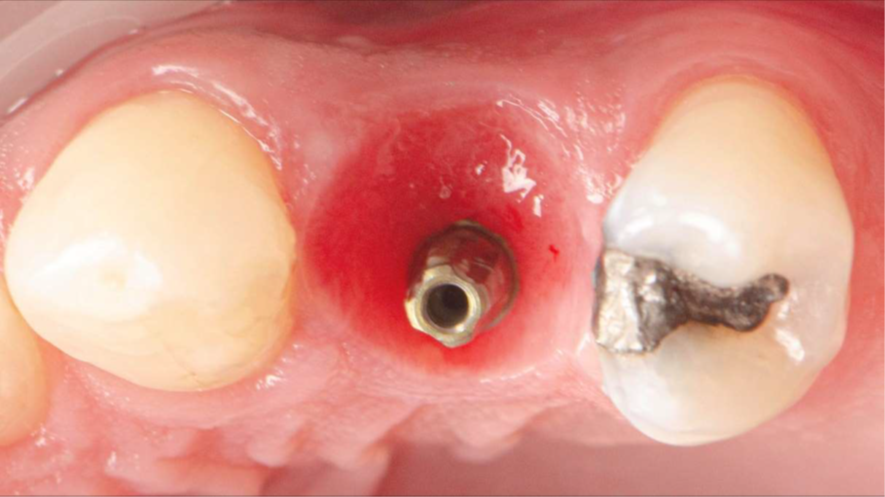

O GAP entre o implante e a parede alveolar foi preenchido com Extra Graft (Hidroxiapatitabovina + 25% colágeno Tipo I). Aqui vale detalhar seu papel biológico:

– a hidroxiapatita atua como matriz osteocondutora, guiando depósito ósseo organizado;

– o colágeno Tipo I melhora manuseio, estabiliza o coágulo, reduz microdeslocamento doenxerto e favorece hemostasia;

– a presença de colágeno também tem efeito quimiotático, atraindo células reparadoras e estimulando cobertura tecidual precoce.

Essa combinação permite a preservação volumétrica do alvéolo, mantendo o suporte ideal para o perfil de emergência natural na fase protética.

Avaliação inicial da estabilidade — ISQ antes do provisório

Antes da instalação do provisório realizou-se leitura com Osstell, fixando o SmartPegdiretamente no implante recém-instalado. O valor obtido foi ISQ > 70, patamar amplamentedescrito na literatura como favorável para protocolos de carga imediata, desde que associadosa controle oclusal e estabilidade protética. Esse ponto é crucial: a decisão não foi tomada combase apenas no tempo, mas em estabilidade primária real e mensurável, reforçando umaconduta guiada por evidência. Somente após ISQ favorável optou-se por provisório funcional.